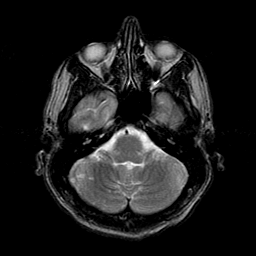

Sarcoma, MR Study #1 mr-t2 -- Slice #4

[Home][Help][Clinical] Slice 4